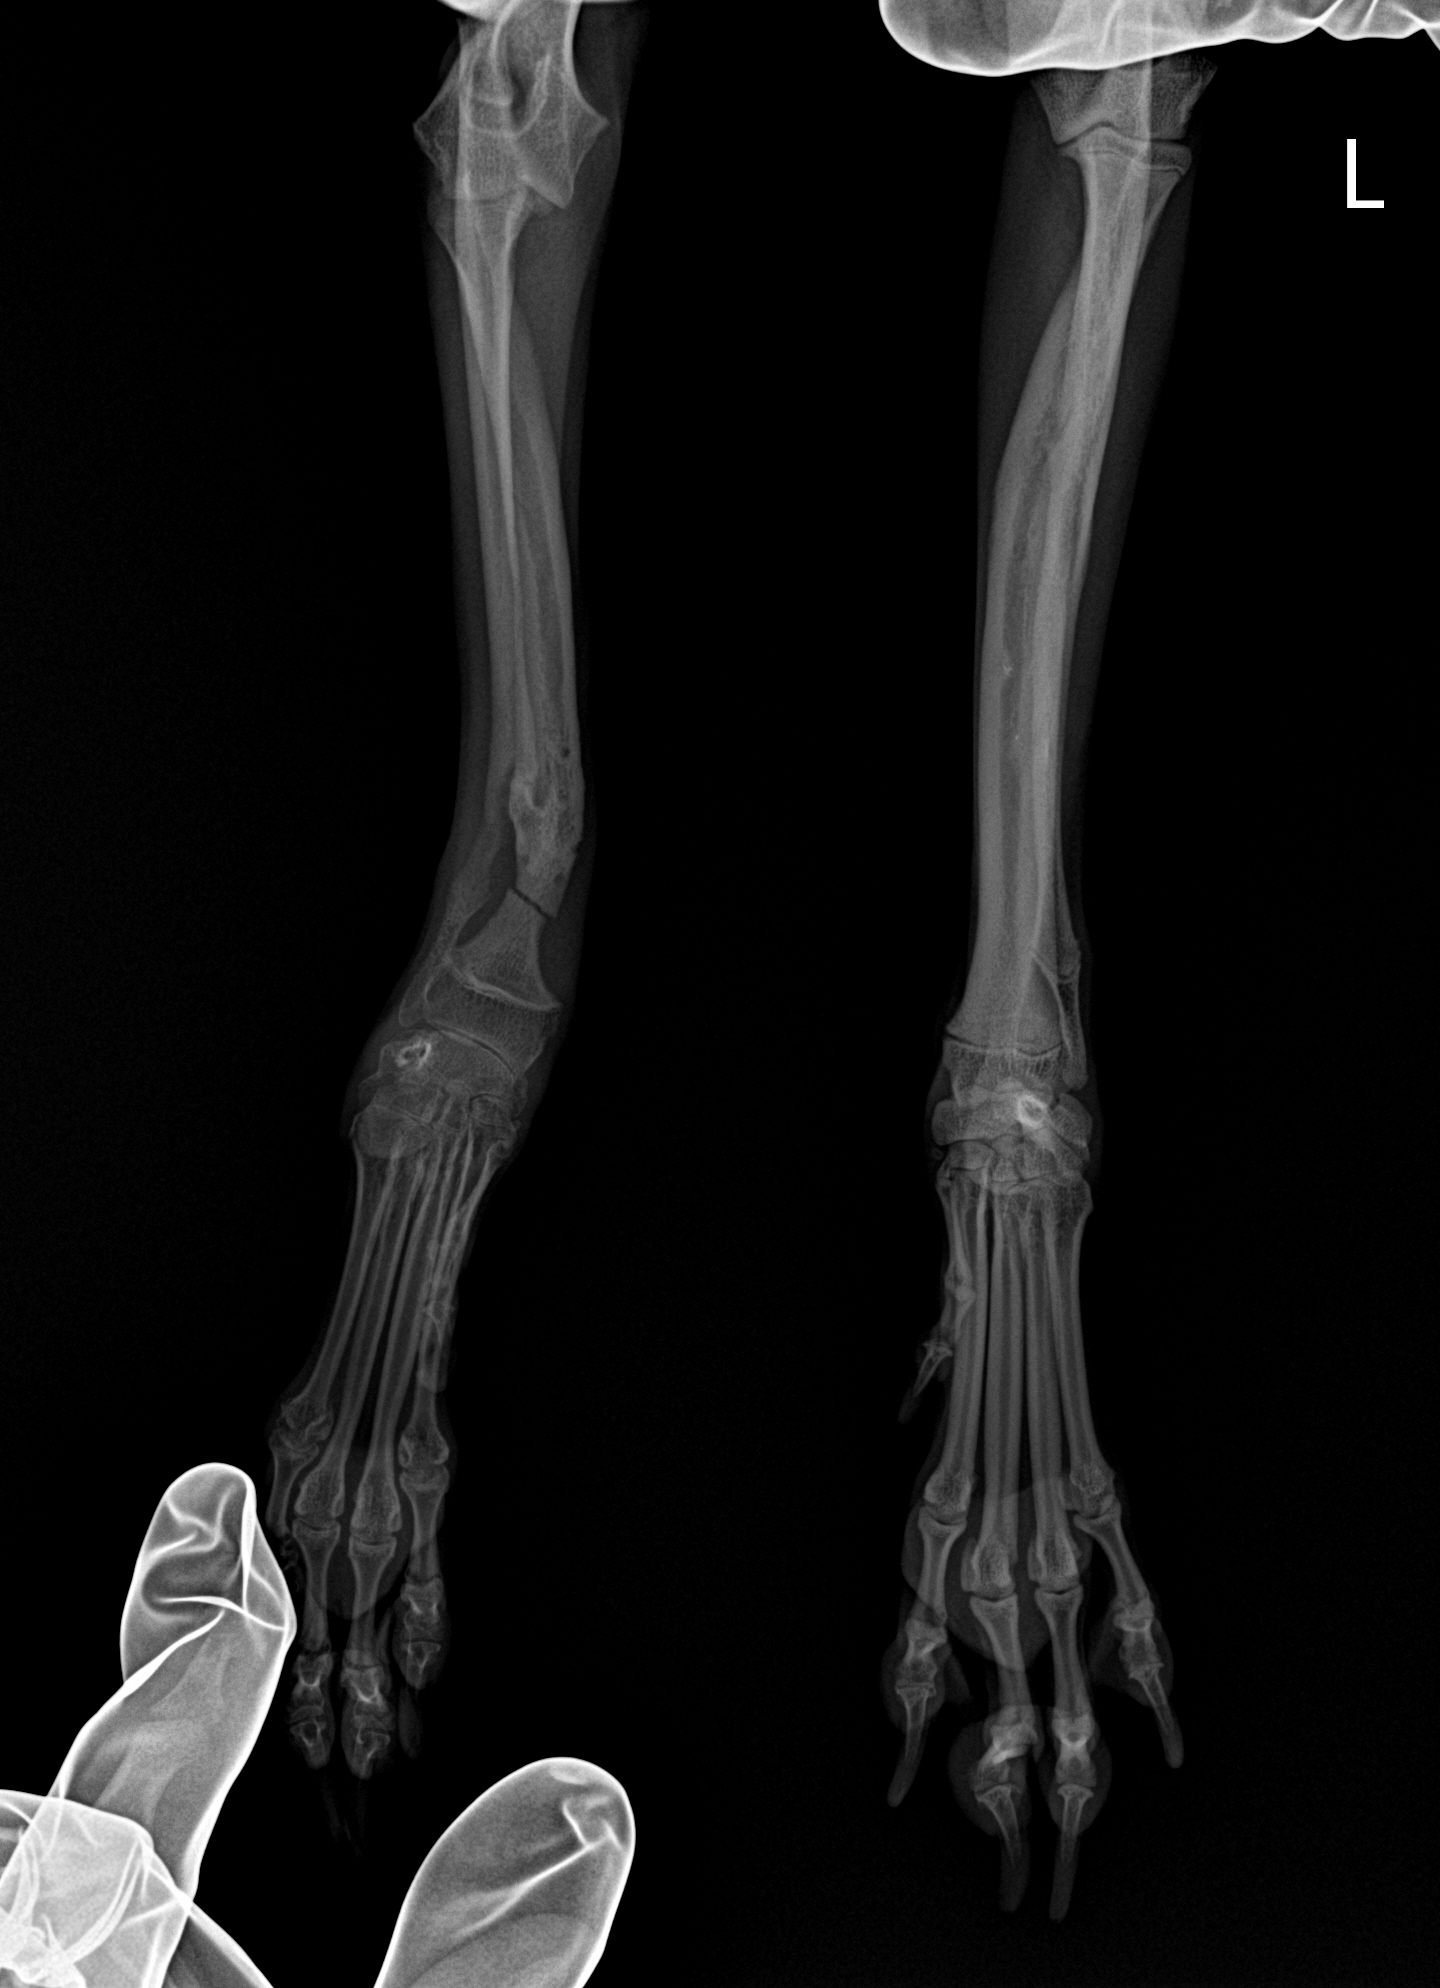

그 주 주말에 결국 재골절이 일어났습니다.

골 재생을 위한 해면골 이식 & 인공뼈 삽입

골절부위 접합을 위한 외고정

이렇게 두 가지의 내용으로 수술을 받았으며 해면골 조직은 수술한 쪽 어깨에서 채취했어요

철심이 몇개가 박힌건진 모르겠지만, 수술 직후 엑스레이를 받아보았을때 저 작고 가느다란 다리에

철심이 몇개씩 박혀있는거 보고 가슴이 철렁했습니다.....

아래 사진에 보이는 뿌옇게 가루같이 보이는게 해면골 조직 입니다